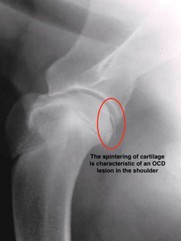

OCD occurs when the cartilage in the joint does not form properly during growth. The affected cartilage becomes thickened, soft, and may break off or detach from the underlying bone. The detachment creates a flap that can cause pain, discomfort, and inflammation as it moves within the joint. Over time, this can lead to degenerative joint disease or arthritis.